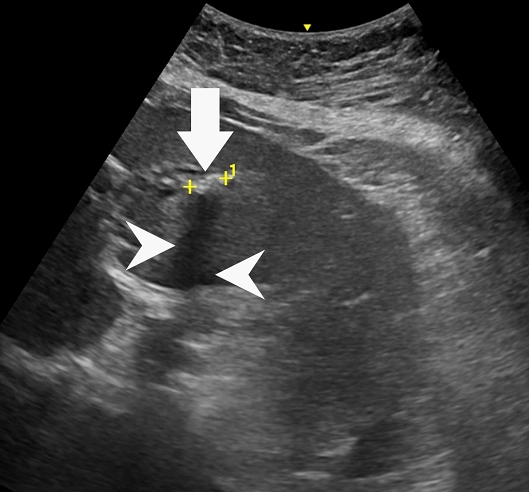

59歲陳女士長期承受間歇性腹痛,九月間於外院住院治療仍無改善,出院後轉至臺中市立老人復健綜合醫院。於肝膽腸胃科由內科部部長賴學洲醫師安排腹部超音波及核磁共振檢查,確診為左側肝內結石合併慢性肝內膽管炎及膽囊細沙併慢性膽囊炎,後經一般外科主任曹連誠醫師評估,安排 3D 立體內視鏡左肝切除加膽囊切除手術。患者術後恢復良好,第二天即可下床行走,自理生活,成功擺脫惱人的腹痛與長年不適。

肝臟及膽道手術過去大多以開腹方式進行,術後疼痛及恢復期長。此次採用的3D 立體內視鏡技術可清晰呈現肝臟內細微結構,3D立體視角搭配螢光血流影像,即時辨識血管與膽管位置,提高手術安全性與精準度。15 公分大的肝臟組織,僅透過約 5 公分傷口取出,可大幅降低術後疼痛與感染風險,縮短住院及復原時間,保留最多肝臟功能,同時避免肝內膽管癌長期風險。